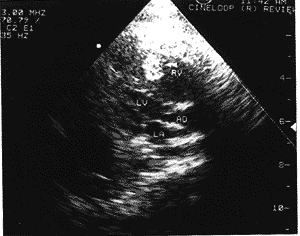

中国超声医学杂志990742 患者28岁,孕1产0。孕38周。平素健康,无遗传性疾病。因不规则宫缩来院就诊。超声 所见:胎头光环显示完整,双顶径9.6cm,脊柱连续良好,胎心率146次/分,胎儿颈部可见 脐带彩环。S/D比值2.8,羊水最大深度5.4cm,胎盘成熟度Ⅱ期。胎儿心脏超声示:左心 长轴及心尖四腔切面均探及右心室内1.5cm×1.2cm大小强回声光团。似乎与乳头肌及腱索 相连(图1)。超声提示:①晚期妊娠头位;②胎儿脐带绕颈;③胎儿右心室实质性肿瘤。不 排除肥大乳头肌。即收入院引产。娩出一死婴。尸体解剖:大体见心脏内有一肿块与乳头肌 及腱索相连。大小1.5cm×1.2cm×0.5cm。病理诊断为右心室内膜下横纹肌瘤。

图1 左室长轴切面 右室(RV)内肿瘤